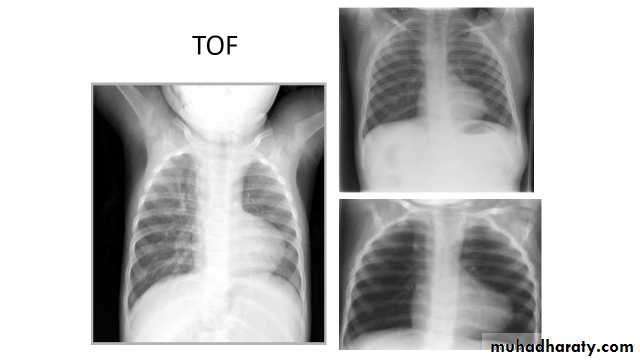

Tetralogy of Fallot (TOF) is one of the most common cyanotic congenital heart conditions and continues to be a major source of morbidity .

Tetralogy of Fallot is classically characterised by four features which are:

ventricular septal defect (VSD) 6

right ventricular outflow tract obstruction (RVOTO) due to:pulmonary artery stenosis

overriding aorta

right ventricular hypertrophy

Radiographic features

Plain filmPlain films may classically show :

"boot shaped" heart with an upturned cardiac apex due to right ventricular hypertrophy and concave pulmonary arterial segment.

Pulmonary oligaemia due to decreased pulmonary arterial flow.

Right sided aortic arch is seen in 25%.